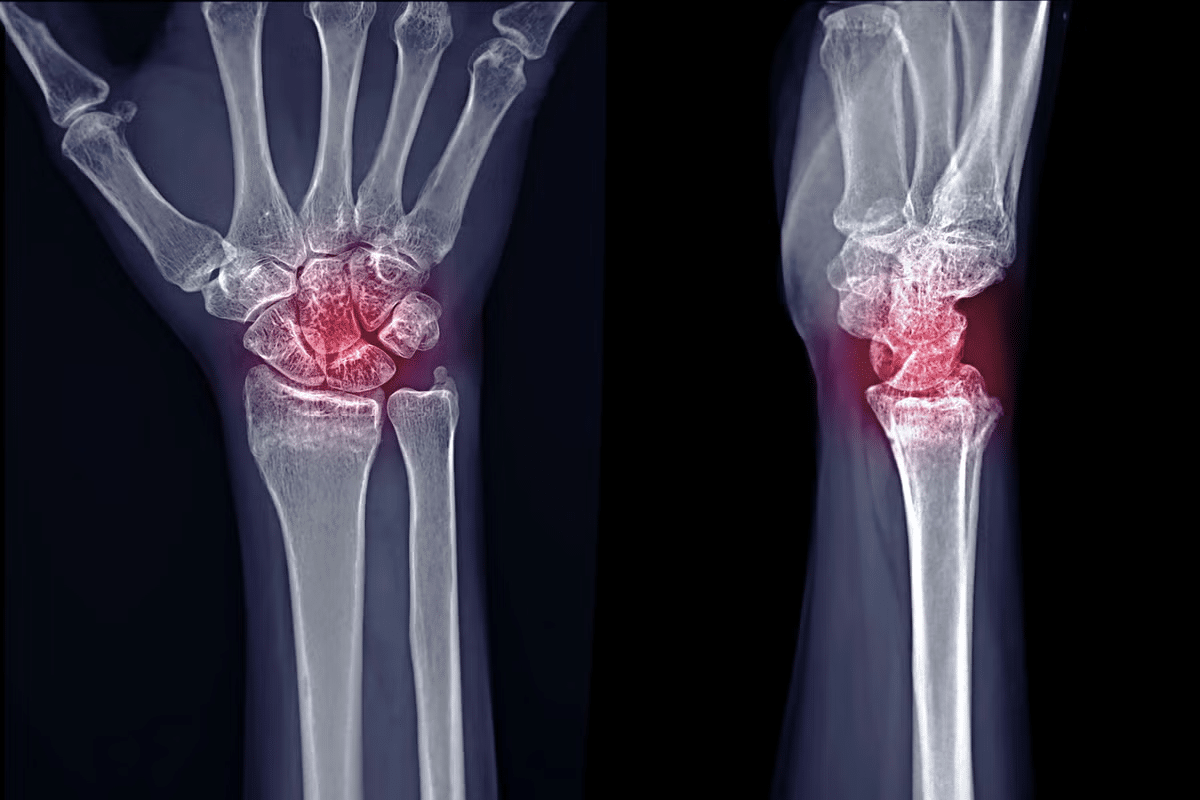

When considering if does arthritis show in an X-ray or does arthritis show on X-ray, it’s essential to understand that X-rays can reveal signs such as joint space narrowing, bone spurs, and erosions. These signs are indicative of various forms of arthritis. The visibility of these signs can depend on the type of arthritis and its stage.

Diagnosing arthritis often starts with looking at X-ray images. We search for specific signs that help us understand the condition’s extent.

Joint space narrowing is a key sign of arthritis on X-rays. It happens when cartilage wears down, reducing the space between bones. This is common in joints like knees and hips, where we see osteoarthritis most.

Bone spurs or osteophytes are another indicator. These are extra bony growths around joints with arthritis. They’re the body’s way to try and stabilize the joint, but they can also cause pain and stiffness.

Bone cysts and sclerosis are also important signs. Bone cysts are fluid-filled sacs in the bone near joints with arthritis. Sclerosis is when bone gets harder, showing up as denser areas on X-rays. Both show the degenerative changes of arthritis.

By looking at these signs on X-rays, we can diagnose arthritis and see how severe it is. Knowing these signs helps us create a treatment plan that fits the patient’s needs.

Arthritis shows up differently on X-rays in various joints. It’s key to know these differences for a correct diagnosis. Each joint affected by arthritis has its own X-ray signs, showing how severe it is.

X-rays are great for spotting damage and changes in the hand and wrist with arthritis. You might see: